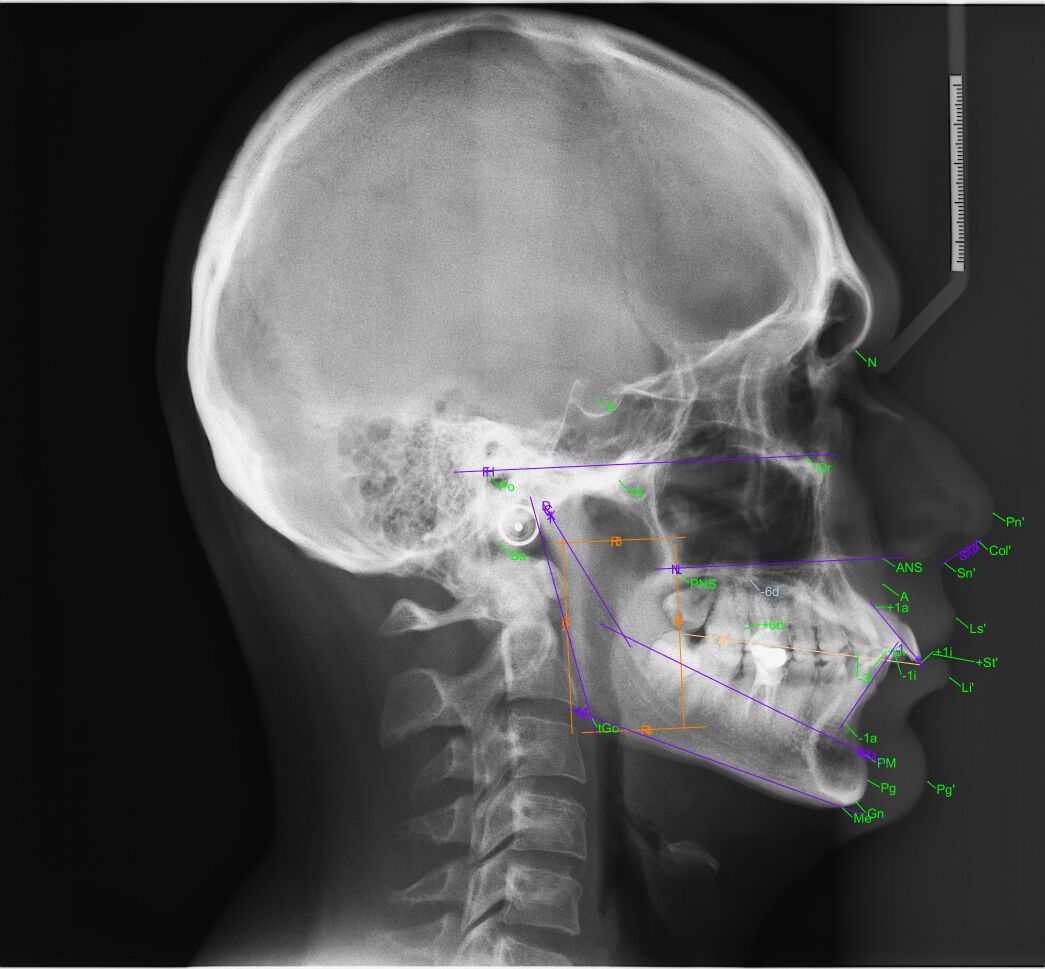

En Panodent contamos con uno de los mejores programas para realizar múltiples análisis cefalométricos, necesarios para la planificación de tratamientos de ortodoncia. Trabajamos con funciones flexibles y fáciles de usar que permiten procesar con precisión los casos más exigentes de ortodoncia y cirugía maxilofacial.